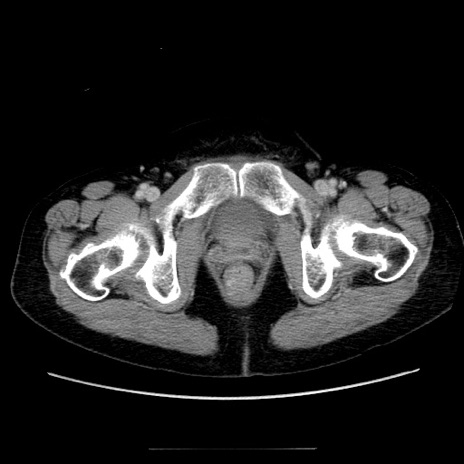

冠状断像

【症例】70歳代女性

【主訴】お腹が張る

【現病歴】1週間くらい前から腹部膨満の自覚あり。昨日夜から増悪したため、本日救急外来受診。

【身体所見】意識清明、BT 36.5℃、BP 165/106mmHg、HR 80bpm、SpO2 98%、腹部:膨満、軟、自発痛・圧痛なし、触診にて不快感あり、腸蠕動音:減弱

【データ】WBC 12600、CRP 1.04